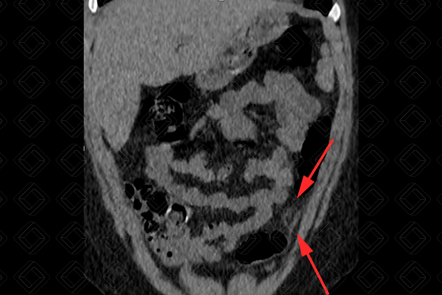

Texto alternativo para a imagem Figuras 1 e 2. Créditos: Dra. Elazir Mota - Rio de Janeiro/RJ

Descrição das figuras 1 e 2: Tomografia computadorizada do abdome superior e pelve. Observa-se uma imagem ovalada, hipodensa, com conteúdo interno gorduroso, na borda anti- mesentérica do cólon, sendo mais comum à esquerda (setas vermelhas). Em geral, associam-se à densificação dos planos adiposos no mesentério.

• Tomografia computadorizada do abdome : Imagem ovalada, paracólica, medindo cerca de 1 a 5 cm, com densidade de gordura e centro radioluscente. Densificação dos planos adiposos perilesional também habitualmente é observada (figura acima).